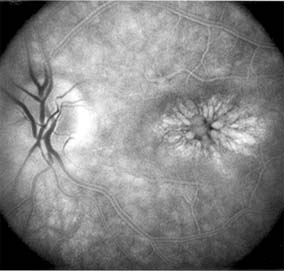

This is a congenital disease of males characterized by a macular lesion called "foveal schisis." On slitlamp examination, foveal schisis appears as small superficial retinal cysts arranged in a stellate pattern accompanied by radial striae centered in the foveal area (Figure 10-14). Visual acuity is usually between 20/40 and 20/200; peripheral visual field abnormalities are present in the 50% of patients with associated peripheral retinoschisis. The posterior pole appears normal on fluorescein angiography, and this may be helpful in the clinical differentiation from cystoid macular edema. B wave abnormalities on the electroretinogram are consistent with the histopathologic finding of intraretinal splitting in the nerve fiber layer.

Figure 10-14

Figure 10-14: X-linked juvenile retinoschisis with typical superficial retinal cysts in the fovea.